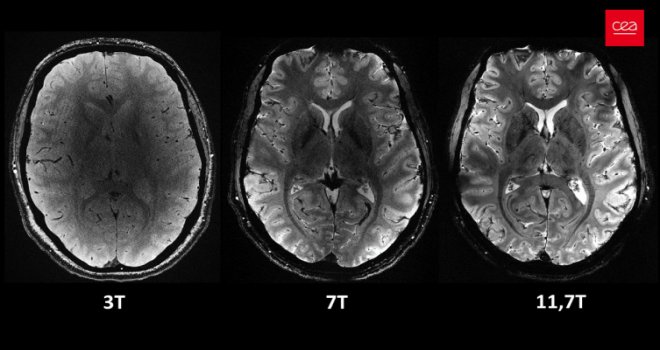

İnsan beyninin en güçlü MRI cihazıyla çekilen en net görüntüsü yayınlandı

CEA'dan yapılan yazılı açıklamada "Iseult" adlı MRI cihazıyla çekilen beyin görüntüsünün 20 yıldan uzun süren bir çalışma sonucu elde edildiği belirtildi.

Yapılan çalışmalar kapsamında MRI cihazının son birkaç ay içerisinde yaklaşık 20 sağlıklı gönüllü üzerinde test edildiği kaydedilen açıklamada, neredeyse 4 dakikada en net beyin görüntüsünün elde edildiği aktarıldı.

Açıklamada, 11,7 Tesla manyetik güce sahip Iseult MRI makinesiyle kısa sürede çekilen görüntülerin, hastanelerde yaygın kullanılan cihazlarla elde edilmesinin saatler sürebileceği kaydedildi.

Iseult Projesi Başkanı ve CEA Araştırma Direktörü Nicolas Boulant, yaptığı açıklamada, verilerin daha yüksek kalitede elde edilebilmesi için araştırmanın birkaç yıl daha devam edeceğini belirterek, hedeflerinin 2026-2030’a kadar nörodejeneratif hastalıkların yanı sıra şizofreni ve bipolar bozukluğu gibi psikiyatri alanındaki birçok hastalığı araştırmak olduğunu ifade etti.

Iseult MRI cihazı ile elde edilen ultra detaylı anatomik bilgilerin, Alzaymır ve Parkinson gibi hastalıkların teşhisinde yardımcı olması bekleniyor.